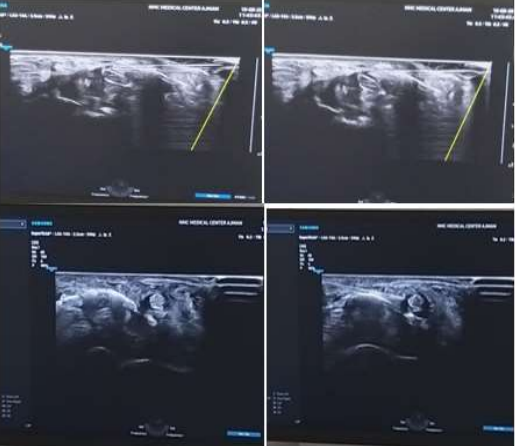

• The transducer is placed in the anatomic axial plane, short axis to the median nerve, identifying the proximal and distal carpal tunnel and any anatomic variants that would prohibit a safe injection (Fig.).

Needle Orientation

• The needle is introduced via an in-plane, ulnar-to-radial approach.

• Alternatively, an out-of-plane, distal-proximal or proximal-to-distal approach can be used with the transducer in the same position (see Fig.).

Target

• Place the needle both superficial and deep to the median nerve at the level of the proximal carpal tunnel (see Fig. ). Anesthetic and sterile saline is used to create a halo around the nerve for the hydrodissection.

• With the alternative out-of-plane approach, the goal is to stay ulnar to the nerve.

Method 1 (in-Plane Approach, Needle Perpendicular to the Long Axis of the Nerve) -

Generally, when using method 1 for HD of nerves, the needle and probe are both perpendicular to the long axis of the nerve. The needle is in-plane to the transducer, and the tissues above and below the nerves are hydrodissected. The needle first approaches the inferior surface of the nerve with the needle bevel positioned up, and the pressure of the injectate is used to open the soft tissues around the nerve layer by layer until the injectate surrounds the epineurium. Since flexible hypodermic needles with bevels are typically used, it is safer to approach the inferior surface of the nerve bevel up as the resistance of the soft tissue will generally force the needle to go deep, and avoid damaging the inferior part of the nerve.28 The same process is repeated with the needle approaching from the superior surface of the nerve, with the needle bevel positioned down (Figure ). The hypodermic needle is bevel down so that the resistance of the soft tissue will force the needle to move more superficial and avoid injuring the superior part of the nerve. The hydrodissected nerve appears oval and surrounded by anechoic fluid on US when the release is completed. A 25-gauge 50 mm, or 22-gauge 70–100 needle is used, depending on the depth of the nerve, and keeping in mind the benefit from an enhanced needle echogenicity that results from reduction of the angle between the probe and the path of needle movement

Method 2 (Out-of-Plane with Subsequent in-Plane Approach-

During the performance of method 2, the needle is parallel to the long axis of the nerve, and the probe is first perpendicular and then parallel to the long axis of the nerve. An “out-of plane” technique is used to HD the nerve from the surrounding tissues, confirming that the nerve is freed from the surrounding soft tissues by the visualization of anechoic fluid surrounding the nerve (both above and below the nerve). Subsequently, the probe is turned “in-plane” toward the nerve, the needle tip is guided back to the top of the nerve, and fluid is injected above it, with the bevel positioned down when approaching the nerve to avoid making accidental contact with the nerve. The injected fluid can accomplish this, but method 2 can separate a comparatively longer length of nerve from surrounding soft tissue through a single insertion point.

• Color Doppler will help visualize the ulnar artery and ensure safe needle placement away from the vasculature.

• An ultrasound can be used for real-time visualization of injectate flow along the nerve by moving the transducer along the length of the nerve.

• A gel standoff is recommended during an in-plane approach to avoid the ulnar artery and nerve.